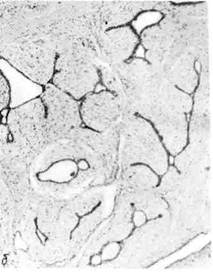

Молочная железа

Органоспецифические опухоли молочной железы отличаются большим

разнообразием и развиваются нередко на фоне дисгормональных доброкаче-

ственных дисплазий. К доброкачественным органоспецифическим опухолям

относят фиброаденому, которая имеет вид инкапсулированного узла

плотной консистенции, волокнистого строения. Микроскопически выявляется

пролиферация альвеол и внутридольковых протоков с разрастанием внутри-

дольковой соединительной ткани. Если она окружает внутридольковые прото-

ки, говорят о периканаликулярной фиброаденоме (рис. 145); при

врастании соединительной ткани в стенку протоков возникают их причуд-

Рис. 145. Фиброаденома молочной железы.

а — периканаликулярная;б интраканаликулярная.

ливые очертания. Такую опухоль называют интраканаликулярной

фиброаденомой (см. рис. 145).